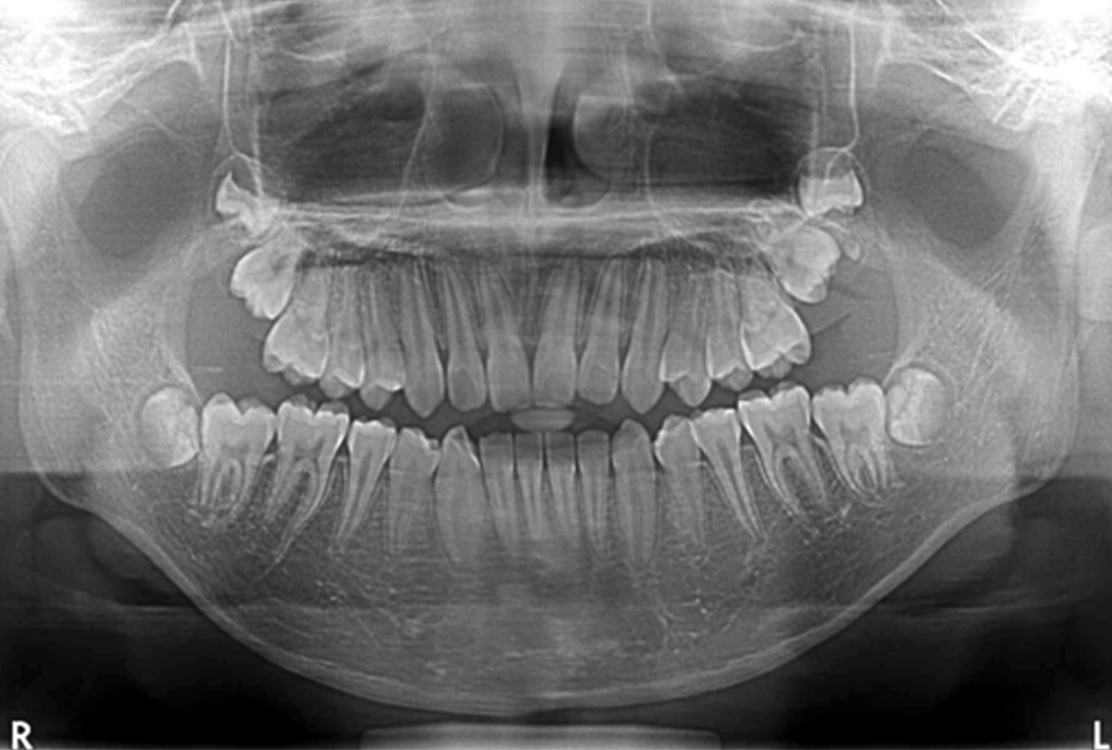

レントゲン画像

| 患者さまの主訴 |

永久歯が生えてこない |

顎顔面矯正 |

| 11歳 |

| 男性 |

2年2ヶ月 |

55万円(税込) |

劣成長の骨格を拡大することで抜歯せずに矯正が行なえる |

トレーニングを頑張らなければ2期矯正が必要になる可能性がある |